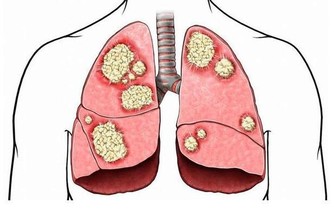

6.骨骼

腿腳靈活運動能力強得5分,偶爾覺得頸椎或腰椎酸痛得3分,很少運動或從來不運動得0分

健康的男性他的骨骼也會很健康,充滿精氣神,熱愛運動,每天再累都會出去健身,所以他們的腿腳很少出現骨骼疾病。而有的人運動頻率少,還長期坐著辦公,時間長了脖子和腰背就會酸痛,關節也容易僵硬。